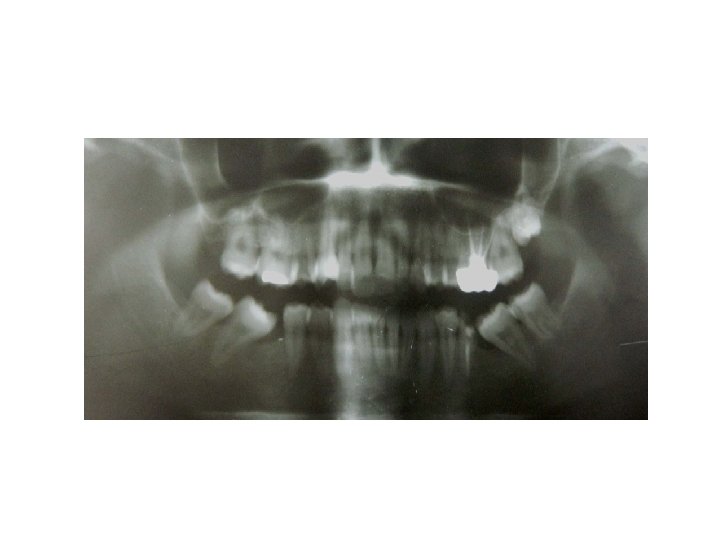

Abutment Evaluation § Abutment is a tooth, portion of tooth or portion of a dental implant that supports or retain a prosthesis § Abutment teeth are called upon to withstand the forces normally directed to the missing teeth, in addition to those usually applied to the abutments • Whenever possible an abutment should be a vital tooth. However, a tooth that has been endodontically treated which is asymptomatic with radiographic evidence of a good seal and complete obturation of the canal can be used as an abutment. If the endodontically treated tooth does not have sound tooth

• The roots and their supporting tissues should be evaluated for 3 factors: • Crown-root ratio • Root configuration • Periodontal ligament area

Periodontal ligament area. Johnston et al in 1971 in their statement designated as “Ante’s law” said that the root surface area of the abutment teeth had to equal or surpass that of the teeth being replaced with pontics

Jepsen in 1963 has reported areas of the root surfaces of the various teeth which is also termed as Jepsen’s rule Root Surface Area (mm) Teeth Maxillary Mandibular Central Incisor 204 154 Lateral 179 168 Canine 273 268 First PM 234 180 Second PM 220 207 First Molar 433 431 Second Molar 431 426